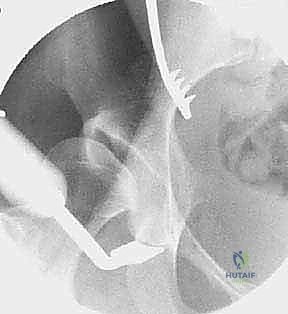

2. الأشعة السينية الرقمية (Digital X-rays): صور في وضعيات محددة (AP Pelvis, False Profile, Dunn view) لقياس زوايا التغطية (مثل زاوية CE وزاوية Tönnis).

4. الأشعة المقطعية ثلاثية الأبعاد (3D CT Scan): تُستخدم للتخطيط الجراحي الدقيق، حيث تتيح للدكتور هطيف بناء نموذج ثلاثي الأبعاد لحوض المريض وتحديد زوايا القطع قبل دخول غرفة العمليات.